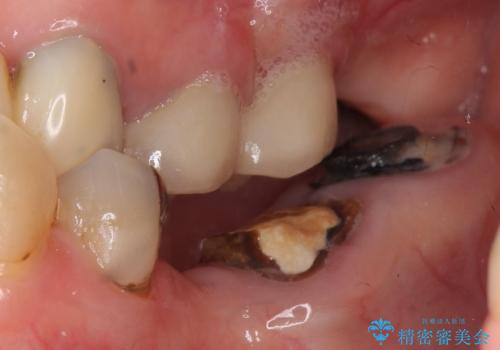

- 奥歯のブリッジの被せ物がとれてしまったとの主訴で来院された患者様です。

奥歯2本は虫歯により残っている健全歯質が少ないため、保存が難しい状態でした。

抜歯してインプラントを提案したところ、「どうしても抜きたくないので残してほしい」と強くご希望されました。

長期的な予後を保証できないことをご了承頂いた上で、歯根分割術、骨外科手術により歯の保存を試みました。